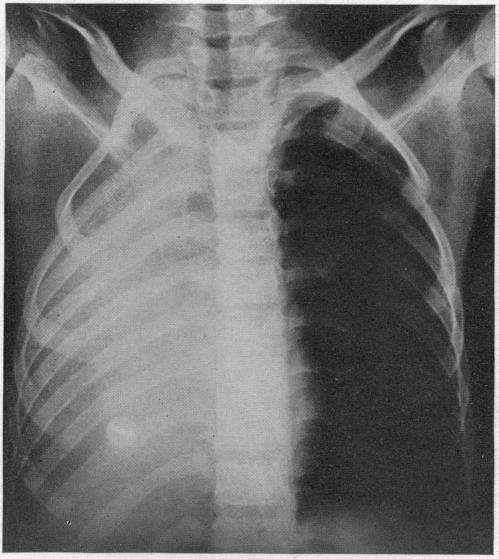

ACUTE MASSIVE COLLAPSE OF THE LUNGS: A DISCUSSION OF ITS MECHANISM AND OF ITS RELATION TO FOREIGN BODIES IN THE BRONCHI AND POST-OPERATIVE COMPLICATIONS.

摘要